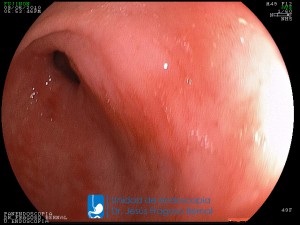

La Unidad de Endoscopía fue creada en 2002 por el Dr. Jesús Fragoso Bernal, es pionera en el estado por la utilización de la tecnología más avanzada, que nos permite ofrecer servicios integrales de diagnóstico y tratamiento para las enfermedades del aparato digestivo.